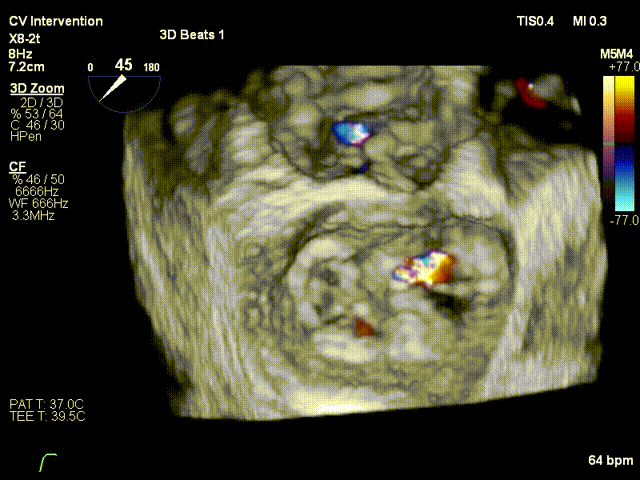

行TEE示:二尖瓣后叶脱垂合并重度反流(DMR4+)。左室后内乳头肌断裂,二尖瓣后叶腱索断裂。二尖瓣前叶长度17.6mm, 后叶有效长度6.1mm,二尖瓣后叶P2区脱垂,MVA 4.63cm²;PISA定量 EROA=0.72cm²。

患者镇静麻醉状态,呼吸机辅助呼吸,ECMO+IABP循环支持,因右侧股静脉入路ECMO占用,遂行左侧股静脉入路,顺利穿刺房间隔,经导管测定左房压力为:41/-3/14mmHg。之后迅速送入经导管二尖瓣钳夹系统,予XTR准确地捕获二尖瓣叶,于A2/P2区域完成夹合,MR4+反流即刻减少至2+;再予NTR定位与残余反流区域,完成二次夹合,反流即刻较少至微量。术中DSA及TEE评估夹合器稳定,遂退出钳夹系统。测定左房压13/-3/1mmHg,较前明显下降,血流动力学稳定,撤处ECMO,保留IABP,手术成功。